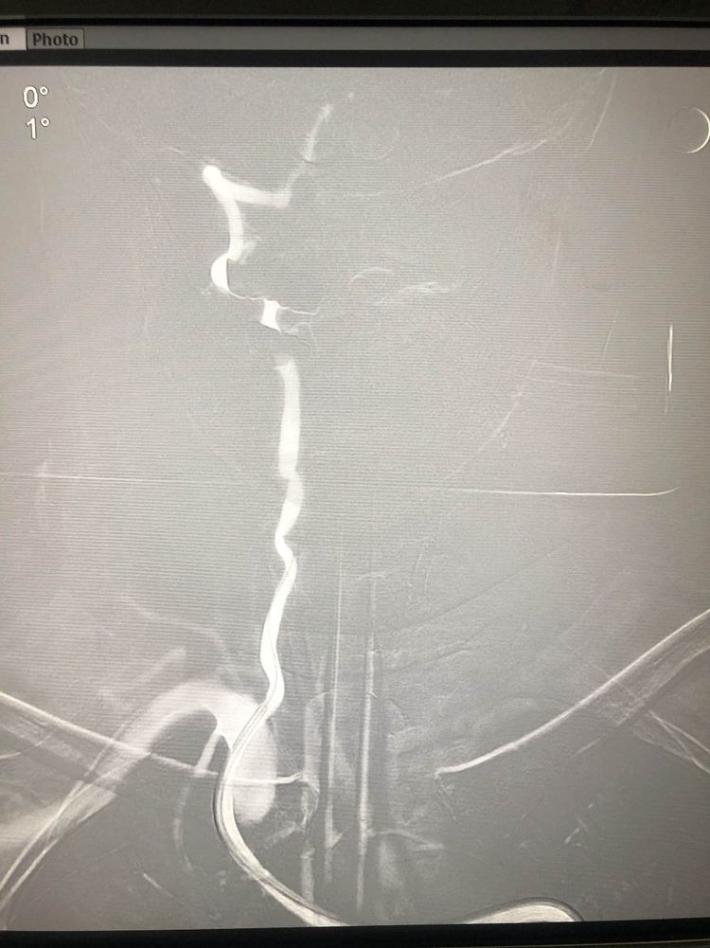

双侧颈内动脉

双侧椎动脉

左侧椎动脉

右侧椎动脉造影:基底动脉中段充盈缺损,基底动脉尖丢失。提示基底动脉中段原位狭窄基础上血栓形成,血栓脱落栓塞基底尖。

微导丝微导管通过闭塞部位,经微导管造影,确认在远端真腔。

一把拉通后,前向血流即刻恢复至3级,双侧小脑上动脉、大脑后动脉、基底动脉尖显影。

现基底动脉残余狭窄约40%,观察20min前向血流3级;斑块累及小脑前下动脉;右侧丘脑出血转化,尽可能避免双抗,综合考虑后放弃急诊支架植入,术后给予盐酸替罗非班泵入维持血流稳定。